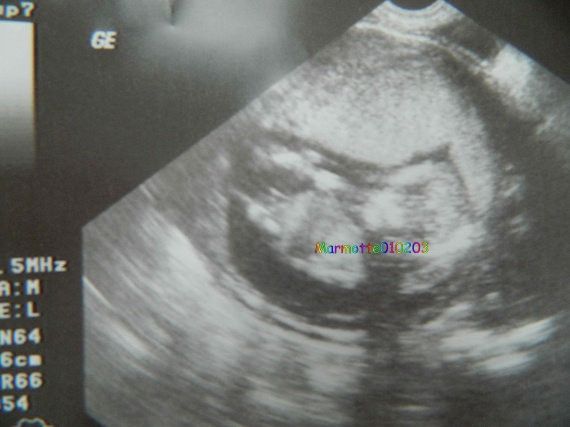

Sentir bebe 14 sa

Sentir bebe 14 saのギャラリー